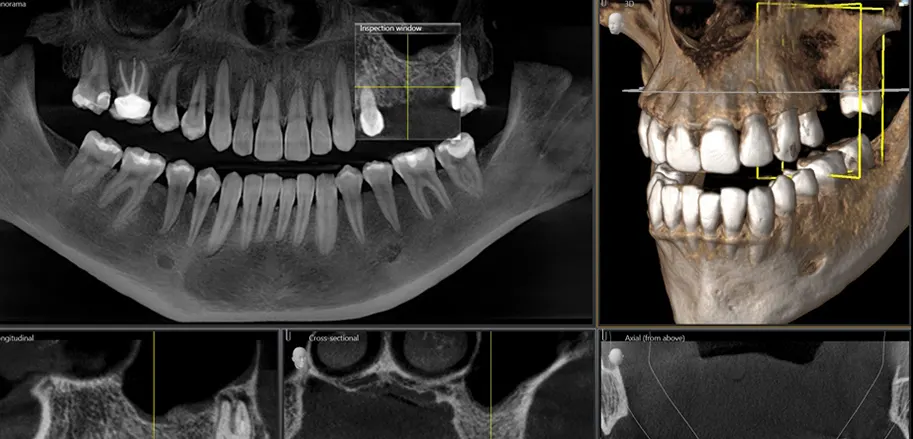

Disponemos de un equipo de CBCT, que es un equipo de Tomografía computarizada de haz cónico (Cone Beam Computed Tomography o CBCT), también conocido como TAC dental.

Es un tipo de prueba diagnóstica que realizamos cuando las radiografías orales no son suficientes para determinar un tratamiento dental. Lo utilizamos en la planificación tratamientos de implantología, endodoncia, prótesis, ortodoncia, y otros muchos casos dónde esta prueba diagnóstica está indicada.

El CBCT nos permite dar un diagnóstico más preciso y en menor tiempo, proporcionándonos imágenes en 3D de la boca del paciente.

El CBCT nos ayuda también en el diagnóstico de la lesiones quísticas, endodónticas, fracturas dentales, aumentos óseos, etc. Para complementar el CBCT, disponemos de equipo de radiografía panorámica y un equipo de radiología intraoral con radiovisografía. Por supuesto, todo ello digital.

El módulo de exploración cefalométrica nos permite ejecutar exámenes cefalométricos de alta calidad en cuestión de segundos. Gracias a este sistema, combinamos una exploracion intraoral con una exploración facial y una exploración CBCT en la misma imagen, una planificación perfecta para prótesis e implantes.